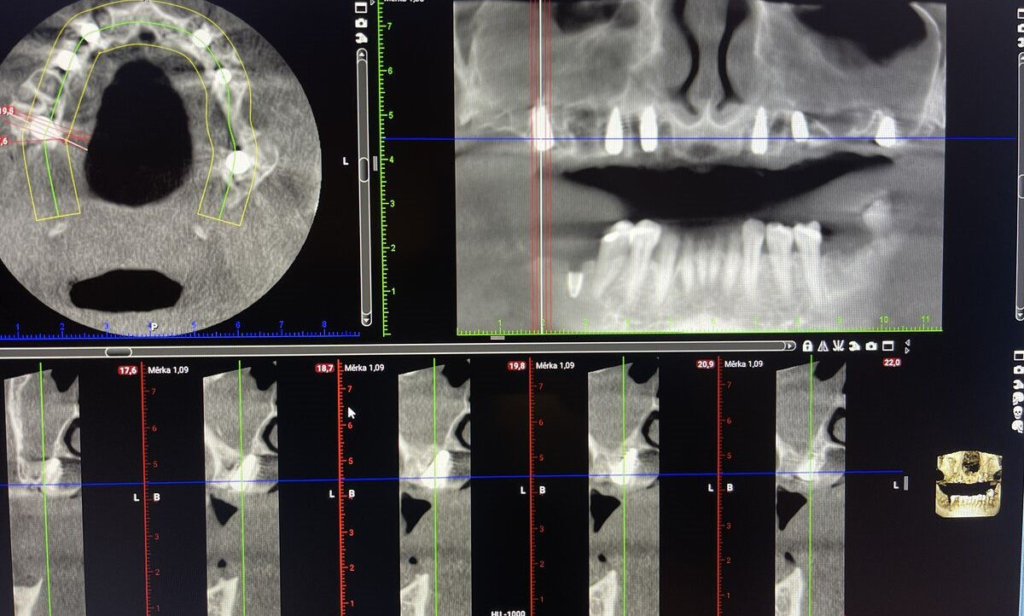

Digitální stomatologie nové generace

- CBCT 3D snímkování, intraorální skener

- CAD/CAM výroba, fotogrammetrie

- maximum přesnosti a přirozený vzhled

- CBCT 3D, vyšetření, fotodokumentace

- volba typu implantátů a finální práce